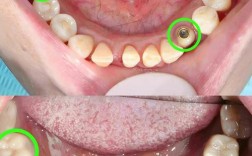

- 上牙可以做种植牙,技术成熟且效果良好。

- 上颌后牙区种植的主要挑战在于解决骨量不足(尤其是高度不足)的问题,常常需要配合上颌窦提升术。

- 上颌骨骨密度较低,愈合时间可能略长于下颌,但成功率依然很高。

- 上颌窦的存在增加了手术的复杂性和风险(如穿孔),需要经验丰富的医生和精确的术前规划(CBCT检查至关重要)。